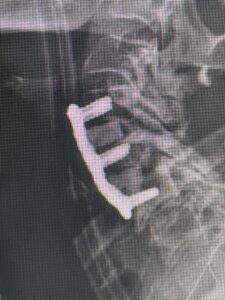

This 59 year-old female had severe bilateral leg pain and numbness over a 6-month period. The patient had failed conservative treatment with physical therapy, chiropractic care, and medications. MRI revealed that she had severe lumbar stenosis with a grade 1 spondylolisthesis or “slipped disc” at L5-S1 (Fig. 2). In addition, she had previously undergone both front and back surgery for severe cervical stenosis where her posterior hardware had failed because of her severe osteoporosis requiring us to remove the posterior hardware. This required her to have an anterior or front operation which allowed better fixation to her spine because of the load-sharing nature of the interbody grafts in addition to her anterior cervical plate (Fig. 3).

(Fig 3) lateral intraoperative cervical x-ray demonstrating good alignment after C4-C6 anterior cervical discectomy and interbody fusion with plate. Note the interbody grafts help load-share the plate in this patient with severe osteoporosis